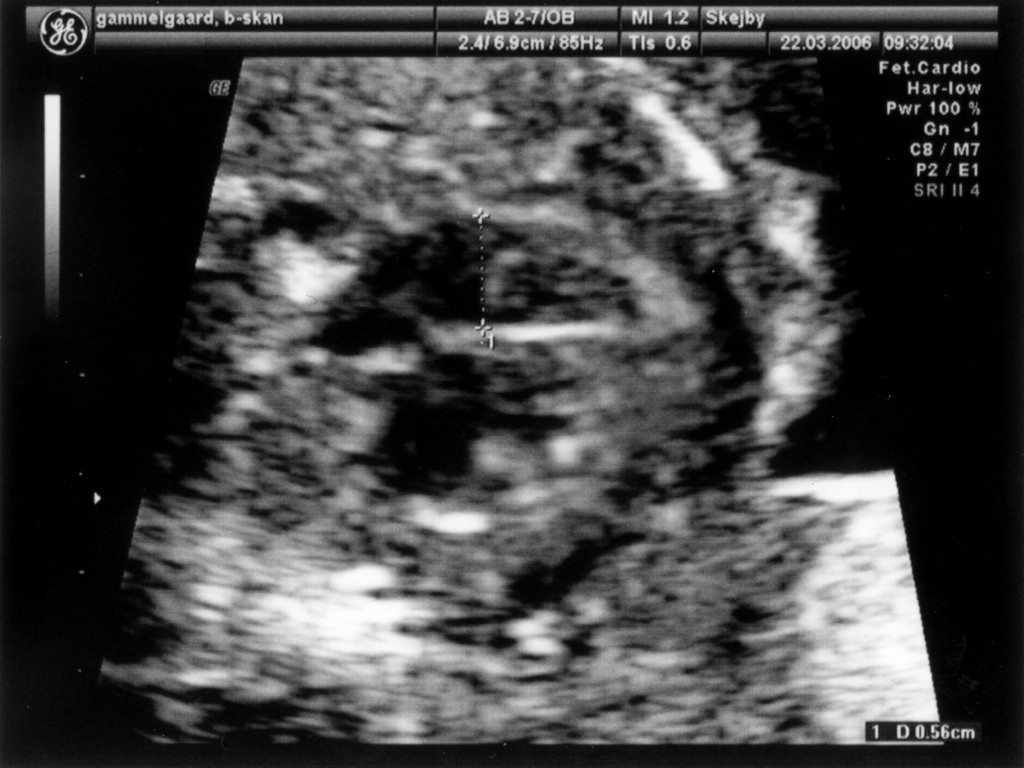

Vi har så endelig været på Skejby Sygehus, hvor specialisterne skulle vurdere babys hjerte. Konklussionen var at baby og hendes hjerte ikke fejler noget - alt er i den skønneste orden. Der blev foretaget en meget grundig skanning og billederne blev vurderet af en afdelingslæge, en overlæge samt en overlæge med mange års international erfaring i børns hjertefejl. Det var en stor lettelse at hun ikke fejler noget. Baby blev undersøgt generelt en gang til at specialisterne og alt er som det skal være. De kunne desuden konstatere, at det er en pige... Du kan se de billeder vi fik fra skanningen herunder.

Baby ligger med hovedet nederst i midten og kigger op. Hun flekser så meget i ryggen at hendes ben går helt op over hovedet. Babys hjerte med nogle målinger.